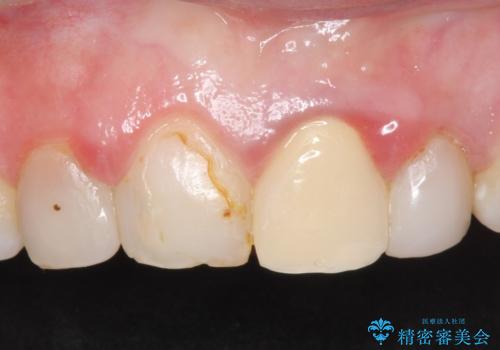

- 前歯の色・形を綺麗にしたいといらっしゃった方の症例です。

左上1、2の再根管治療終了後、オールセラミッククラウン(スペシャル)による補綴を行いました。